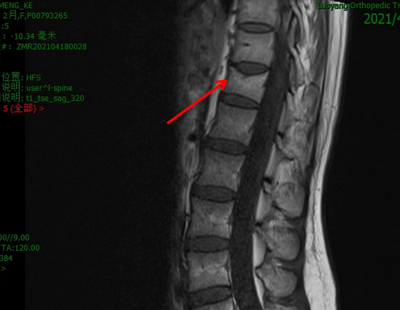

这是河南省洛阳正骨医院叶进主任遇到的一个案例,27岁宝妈分娩后三天出现腰背部酸困疼痛的情况,疼痛严重时无法起床、翻身,活动功能受限。产后三个月,宝妈到医院检查,腰椎检查提示T12椎体压缩性性骨折;骨密度检查显示其腰椎骨密度和肱骨近端骨密度相当于50多岁成年人的骨密度,这个结果令所有人大吃一惊!

腰椎MRI检查